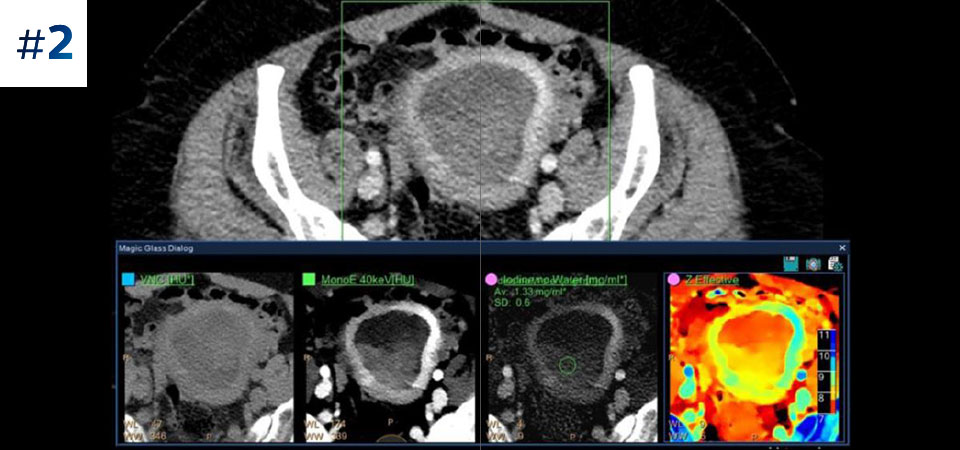

Moins d'examens complémentaires Une meilleure caractérisation et visualisation des tissus contribuent à réduire le besoin d'investigation complémentaire notamment lors de découvertes fortuites.

Allez plus loin que l'imagerie conventionnelle. Constatez par vous-même la pertinence de l'imagerie spectrale à la détection pour améliorer votre confiance diagnostique.

Voir la différence entre le scanner conventionnel et la détection spectrale